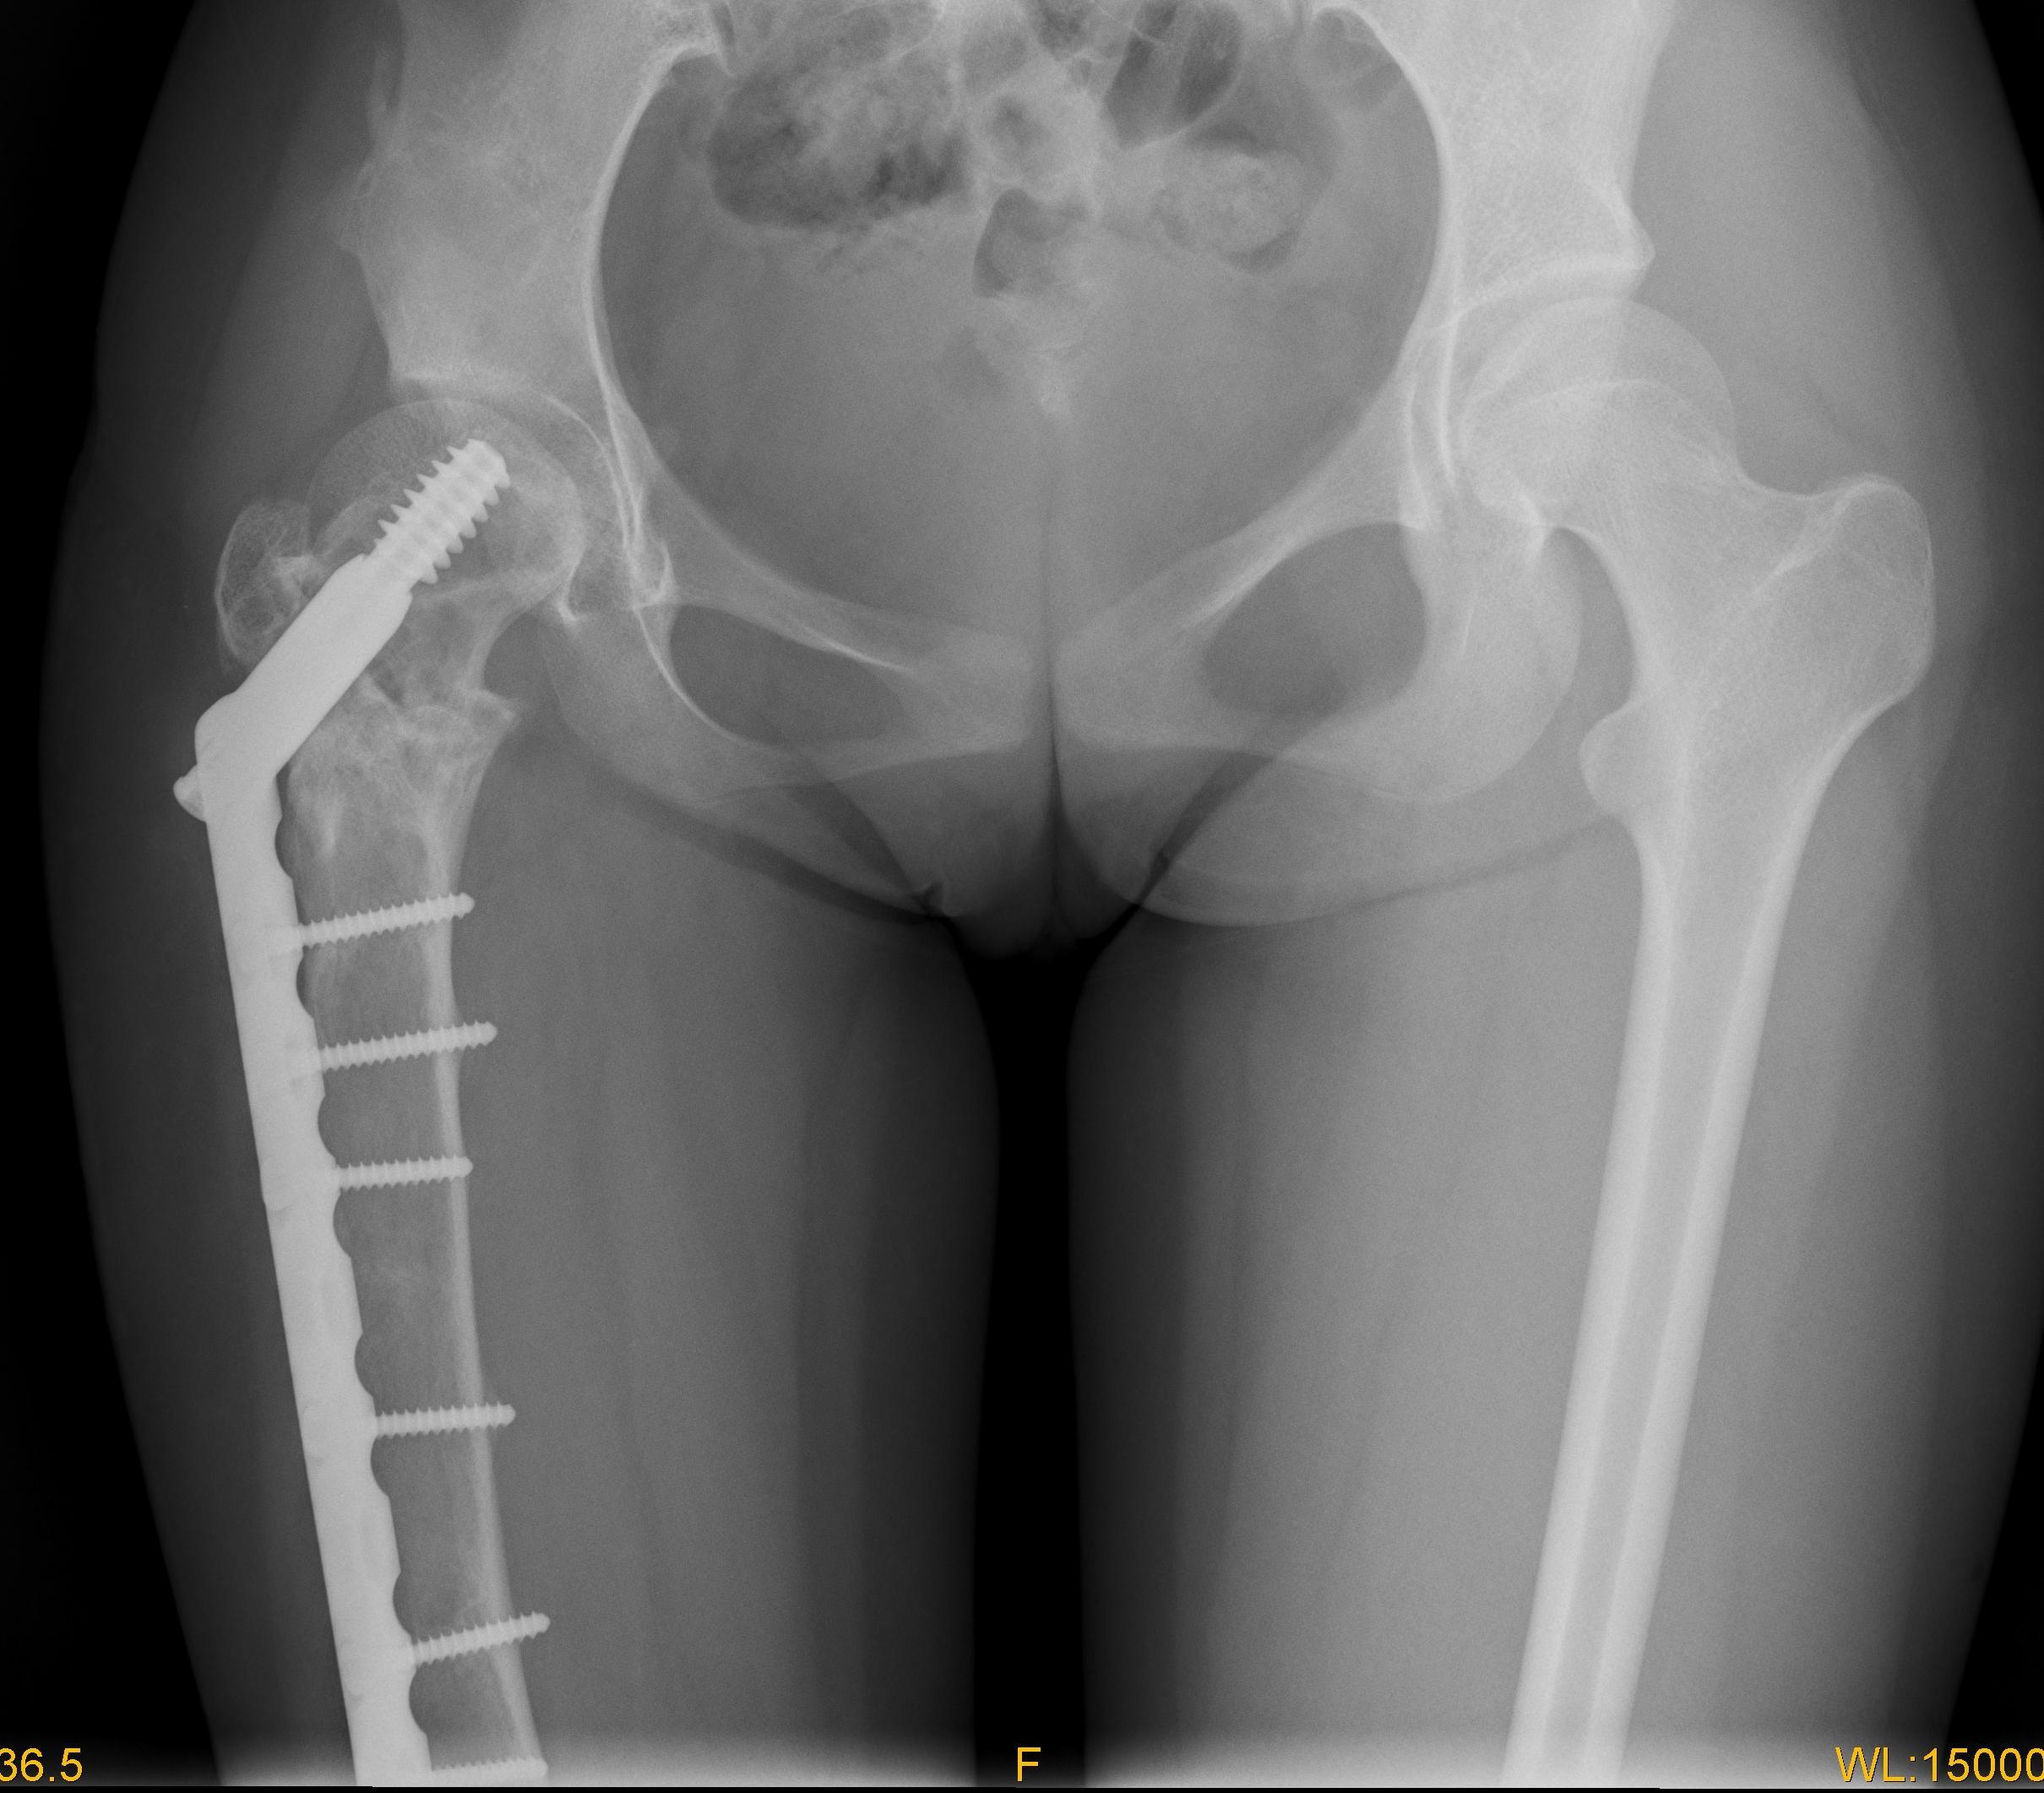

图3 术后肢体等长

图4 女性,17岁,术前肢体短缩4cm图5 术后2年复查肢体等长,截骨处愈合